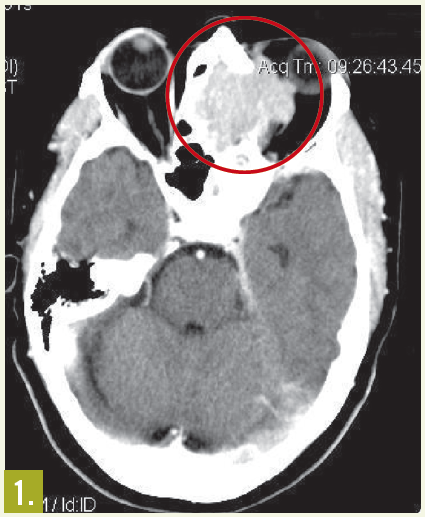

Physical examination. The patient had moderate proptosis; extraocular motions of the left eye were restricted in all directions. She had no lymphadenopathy. Oropharynx was visually unremarkable; however, fiberoptic nasopharyngoscopy revealed a posterior superior nasal cavity mass. A contrast CT scan of the head showed a large mass lesion at the level of the ethmoid sinus, eroding into the left orbit and displacing the left globe (Figure 1).

MRI of the head showed a 5.3 cm x 4.2 cm x 4.2 cm enhancing mass at the base of the brain that extended into the nasal cavity, with erosion into the cribriform plate, ethmoid sinuses, and planum sphenoidale.

Results of an ethmoid sinus mass biopsy confirmed high-grade diffuse large B-cell lymphoma. Staging CT scans showed no metastatic disease, and cerebrospinal fluid analysis revealed no malignant cells. A bone marrow biopsy specimen showed no evidence of light chain monoclonality, no overt evidence of B-cell lymphoproliferative disorder on flow cytometry analysis, and no lymphoma. This was consistent with stage IAE disease.

Outcome of the case. In this patient, treatment with rituximab, cyclophosphamide, doxorubicin, vincristine, and prednisone chemotherapy for 6 cycles resulted in excellent clinical and radiological response (Figure 2).